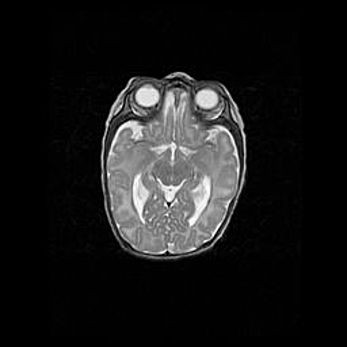

Наружная гидроцефалия с возможной атрофией височных областей.

Возраст: 28 дней

Вес: 3670 г

Пол: мужской

Окружность головы: 38 см

Срок гестации: 40 недель

Гидроцефалия головного мозга у новорожденных – это заболевание, которое характеризуется скоплением избыточного количества спинномозговой жидкости в желудочковой системе головного мозга в результате затруднения её перемещения от места выработки к месту поглощения в кровеносную систему или вследствие нарушения абсорбции. При открытой наружной форме гидроцефалии у новорожденных расширяются и переполняются субарахноидные пространства.

При нормотензивных  формах,  которые,  как  правило,  являются  следствием  перенесенных ишемических  повреждений  паренхимы  мозга,  возможно  сочетание микроцефалии  с нормотензивной гидроцефалией. В основе данных изменений лежит атрофия больших полушарий с преимущественной  локализацией  в  лобно-височных  областях.